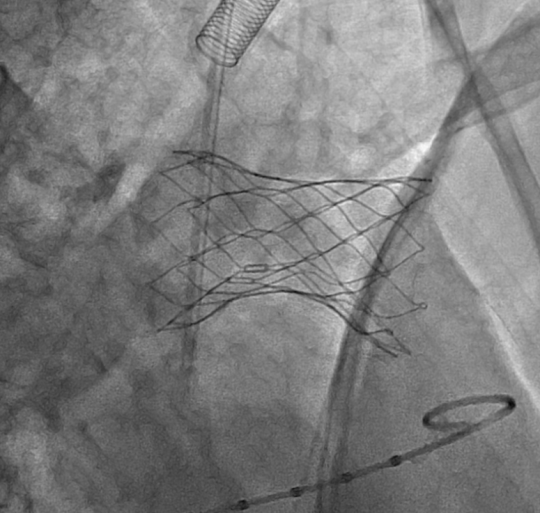

在安琪教授的主持下,多学科讨论后认为该患者上述解剖特点不适合目前经股静脉入路植入的介入肺动脉瓣,可考虑使用佰仁医疗Salus介入肺动脉瓣经心尖入路实施肺动脉瓣植入。在心脏大血管外科安琪教授主持下,心脏内科冯沅教授带领赵振刚副教授及李翔医师与心脏大血管外科罗书画副主任医师及李东旭主治医师合作完成了手术。术中手术团队经股静脉完成心导管检查及造影后,通过肋间小切口暴露右室心尖并预置荷包缝线,穿刺右室心尖建立经心尖入路,而后分别经股静脉和心尖进行左、右肺动脉球囊对吻扩张,最后经心尖完成肺动脉瓣植入。术后TEE提示肺动脉瓣植入位置理想、固定良好,无瓣周漏或中央反流,左、右肺动脉显影正常。肋间切口长度仅2.5cm,总体手术效果满意。

肺动脉瓣膜植入后